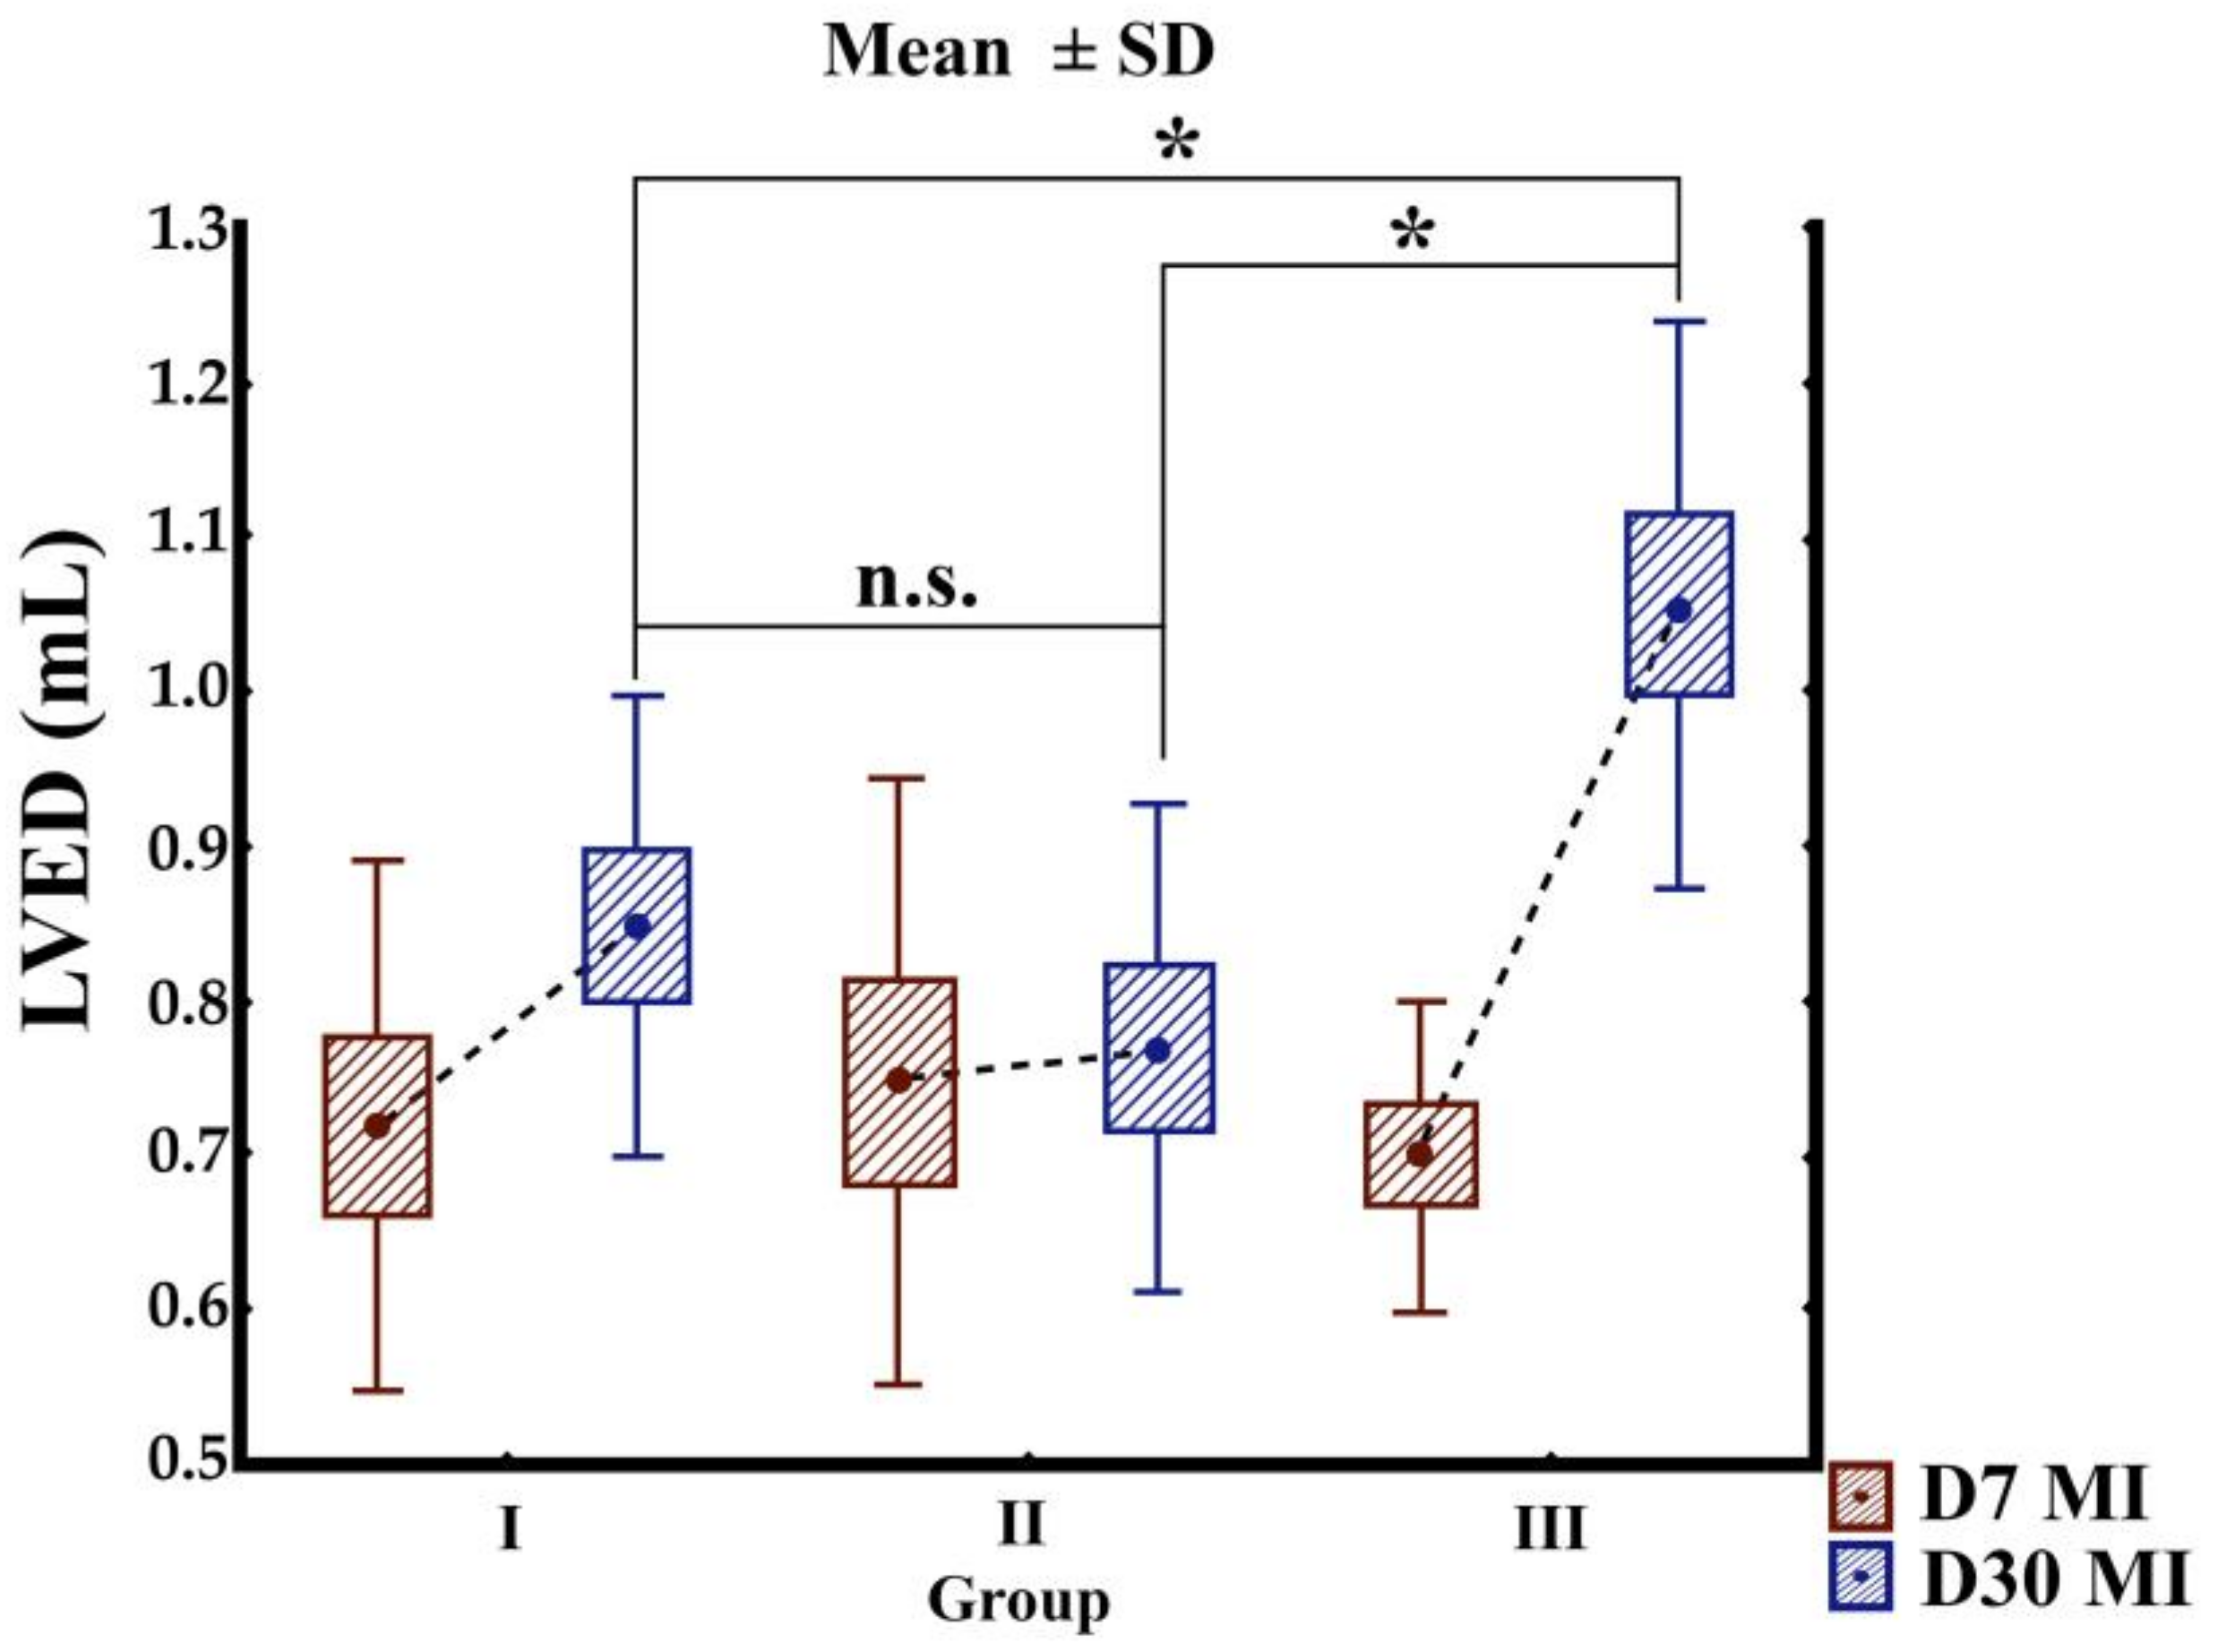

3.2. Echocardiographic Findings

| Variable | Group | D7 | D30 | p-Value (D7 vs. D30) |

|---|---|---|---|---|

| LVEF (%) | I | 28.21 ± 5.07 | 32.72 ± 8.62 | 0.316 |

| II | 22.79 ± 5.80 | 26.74 ± 4.92 | 0.065 | |

| III | 27.37 ± 8.40 | 27.92 ± 9.77 | 0.865 | |

| LVES (mL) | I | 0.509 ± 0.106 | 0.582 ± 0.149 | 0.241 |

| II | 0.596 ± 0.171 | 0.598 ± 0.141 | 0.982 | |

| III | 0.514 ± 0.112 | 0.780 ± 0.206 | 0.001 * | |

| LVED(mL) | I | 0.718 ± 0.170 | 0.848 ± 0.149 | 0.326 |

| II | 0.747 ± 0.196 | 0.768 ± 0.158 | 0.043 | |

| III | 0.698 ± 0.102 | 1.056 ± 0.183 | 0.004 * |